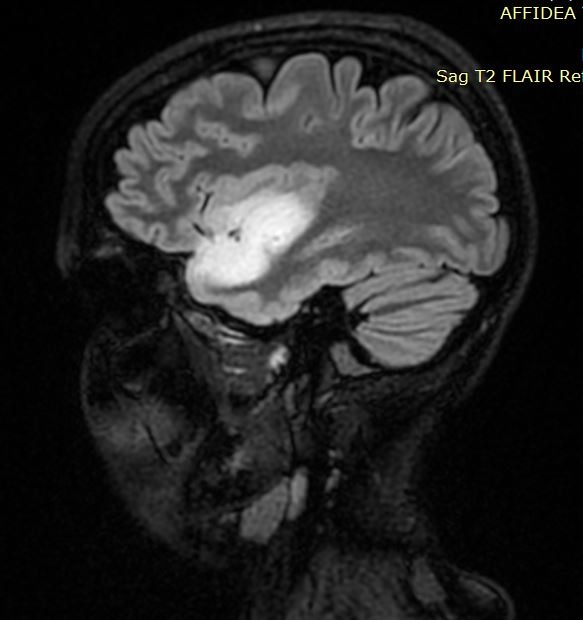

Ο έλεγχος με μαγνητική έδειξε όγκο στο αριστερό ημισφάιριο, σε δύσκολο σημείο, τόσο λειτουργικά όσο και χειρουργικά.

Αφού έγινε ένας ενδελεχής έλεγχος με μαγνητική δεσμιδογραφία (ώστε να δούμε από που ακριβώς περνάνε τα σημαντικά νευρικά δεμάτια) καθώς επίσης και λειτουργική μαγνητική (ώστε να δούμε πόσο κοντά στα κέντρα της ομιλίας ήταν ο όγκος), αποφασίστηκε η διενέργεια κρανιοτομίας με την ασθενή ξύπνια (awake craniotomy), με τη χρήση διεγχειρητικού υπερήχου,και διεγχειρητικού νευροφυσιολογικού ελέγχου (neuromonitoring).